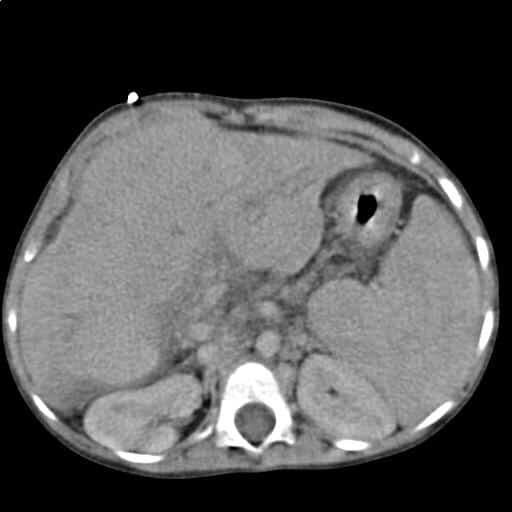

Для дополнительной диагностики применяют КТ или МРТ брюшной полости, на которых можно отчетливо увидеть диффузные изменения печени по типу жировой инфильтрации, обнаружить возможные дополнительные патологии. Выполнение биопсии позволяет детально изучить ткани и содействует разработке плана лечения, чтобы понять, какие дозировки лекарств следует назначить.